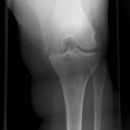

Kniegelenk

Knie a.-p (1. Ebene)

Fraktur, Luxation, entzündliche und degenerative Veränderungen

Bein gestreckt und leicht nach innenrotiert, sodass die Epicondylen auf einer Höhe sind (Patella mittelständig)

Häufiger Fehler: Gelenkspalt nicht frei projiziert, durch zu starke Außenrotation bzw. zu starke Innenrotation.

Kniegelenkspalt muss frei abgebildet sein, Tibiaplateau lateral muss strichförmig dargestellt werden, medial leicht oval, Kniescheibe mittelständig.